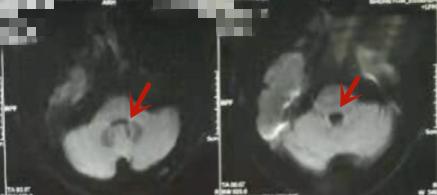

复查颅脑MRI+MRA示:桥脑对称性长T1长T2信号,DWI高信号影,横断面上呈蝴蝶形、冠状面上呈蝙蝠翅膀样(见图2)符合CPM表现,以“脑桥中央髓鞘溶解综合症”收入院。

图2

CPM影像学特点:此病变在脑桥中央呈现对称性特点, CT影像学特点表现为脑桥中央对称性低密度病灶,此部位因结构特点存在一定伪影,病灶显示不清晰。MRI特点主要是脑桥基底部中央对称性异常信号,T1WI序列提示等、低信号,T2WI及T2FLAIR序列提示高信号,边界清,形态各异。

MRI与CT相比,在诊断脑桥中央髓鞘溶解症上更灵敏,而且临床诊断中通常出现CT诊断结果为阴性,而MRI诊断结果为阳性。因此对于高度怀疑CMP患者,应及时行MRI检测。